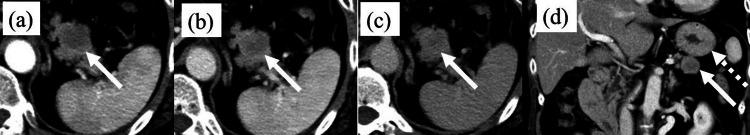

Cancer (including pancreatic cancer) can develop following a infection within one year of tuberculosis infection. However, it is unclear whether tuberculosis infection increases the risk of developing adenosquamous carcinoma of the pancreas (ASCP), an extremely rare cancer with a poorer prognosis than pancreatic ductal adenocarcinoma (PDAC). Herein, we report a case of rapid growing ASCP discovered upon a resection for neck tuberculous lymphadenitis. The patient was a 57-year-old woman. An excisional biopsy of the swollen right neck lymph nodes revealed tuberculous lymphadenitis. One month after the biopsy, an abdominal computed tomography scan showed a 2.0 cm (diameter) ischemic tumor in the pancreatic tail. The tissue obtained using endoscopic ultrasonography-guided fine-needle aspiration led to the pathological diagnosis of ASCP. Two months after the biopsy, the tumor had grown to 3.5 cm (diameter), and invasion of the stomach and colon was suspected. Distal pancreatectomy, splenectomy, partial gastrectomy, and transverse colectomy were performed. The final diagnosis was ASCP (4.7 cm, pT3, pN0, cM0, and pStage IIA). Postoperative adjuvant combination chemotherapy combined with antituberculosis drugs was administered orally. We report the first case of rapidly growing adenosquamous carcinoma resected from the pancreas in association with tuberculous lymphadenitis. Additional evidence is needed to confirm that tuberculosis infection increases the risk of developing pancreatic adenosquamous cell carcinoma because its potential role in promoting squamous metaplasia is unclear.

摘要